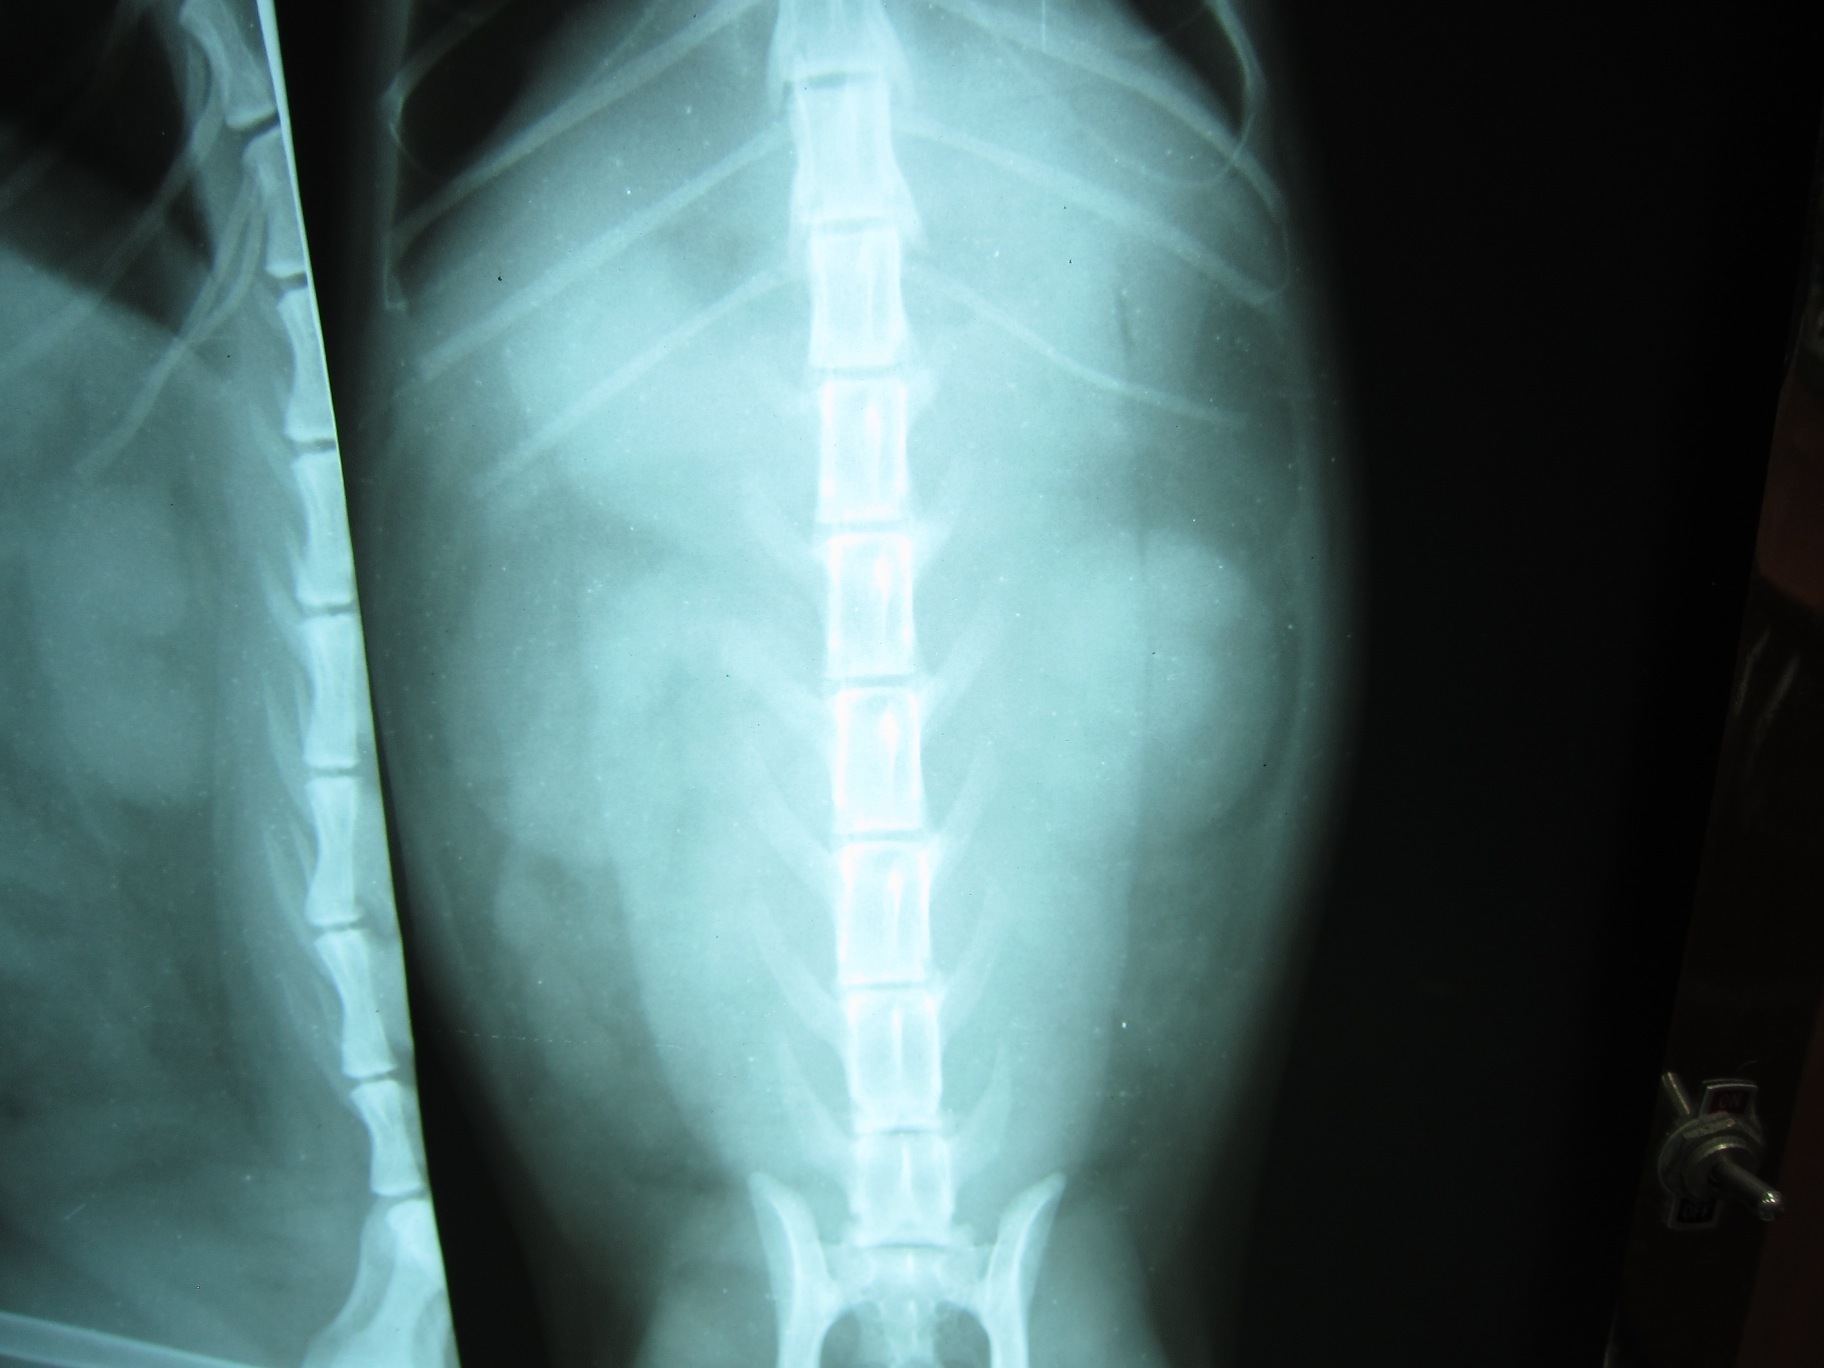

照完X光後,醫師發現有內出血,胰臟破裂,氣胸,有一部分的肝也破了,腎臟也受傷等等狀況。因為實在傷得很重,心跳跟呼吸也都漸漸微弱,只能靠吸氧氣支撐。不過最後還是撐不住就走了。動物近況說明: 他本來是社區貓,一直都跟不太友善的人類相安無事。